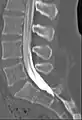

Myelogram showing arachnoiditis in the lumbar spine. | |